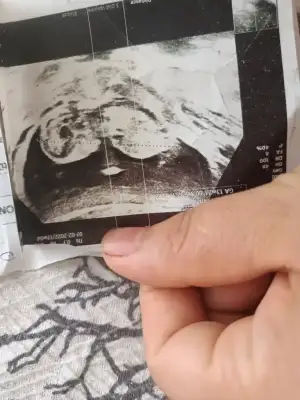

Erkek seninkiBenimkinde tahmin Edermisiniz 15 haftlik

Seninki daha küçük ama keseye ben pek inanmıyorum benim kese resmen fasulye gibiydi erkeek dediler ama benim prensesim olcakKızlar keseden cinsiyet tahmini diye birşey varmış atıyorum bakın

Erkek sanki benim oğlumun kesesine benziyir biraz bidr benimkide böyle sağ taraftaydiEvt cnm karından bakildi

Hayrlisi artikErkek sanki benim oğlumun kesesine benziyir biraz bidr benimkide böyle sağ taraftaydi